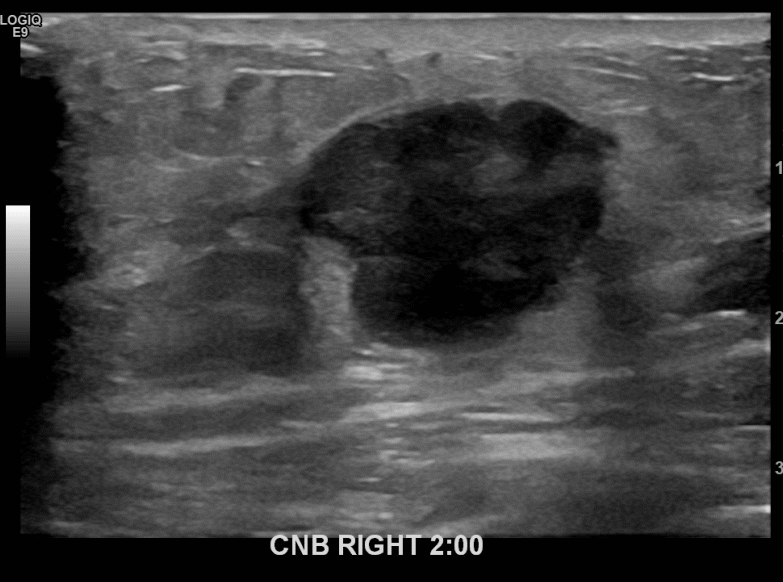

상기환자 외부건진이상소견으로 내원하신 60대 여성분으로 조직검사시행후

유방암진단되셨습니다.